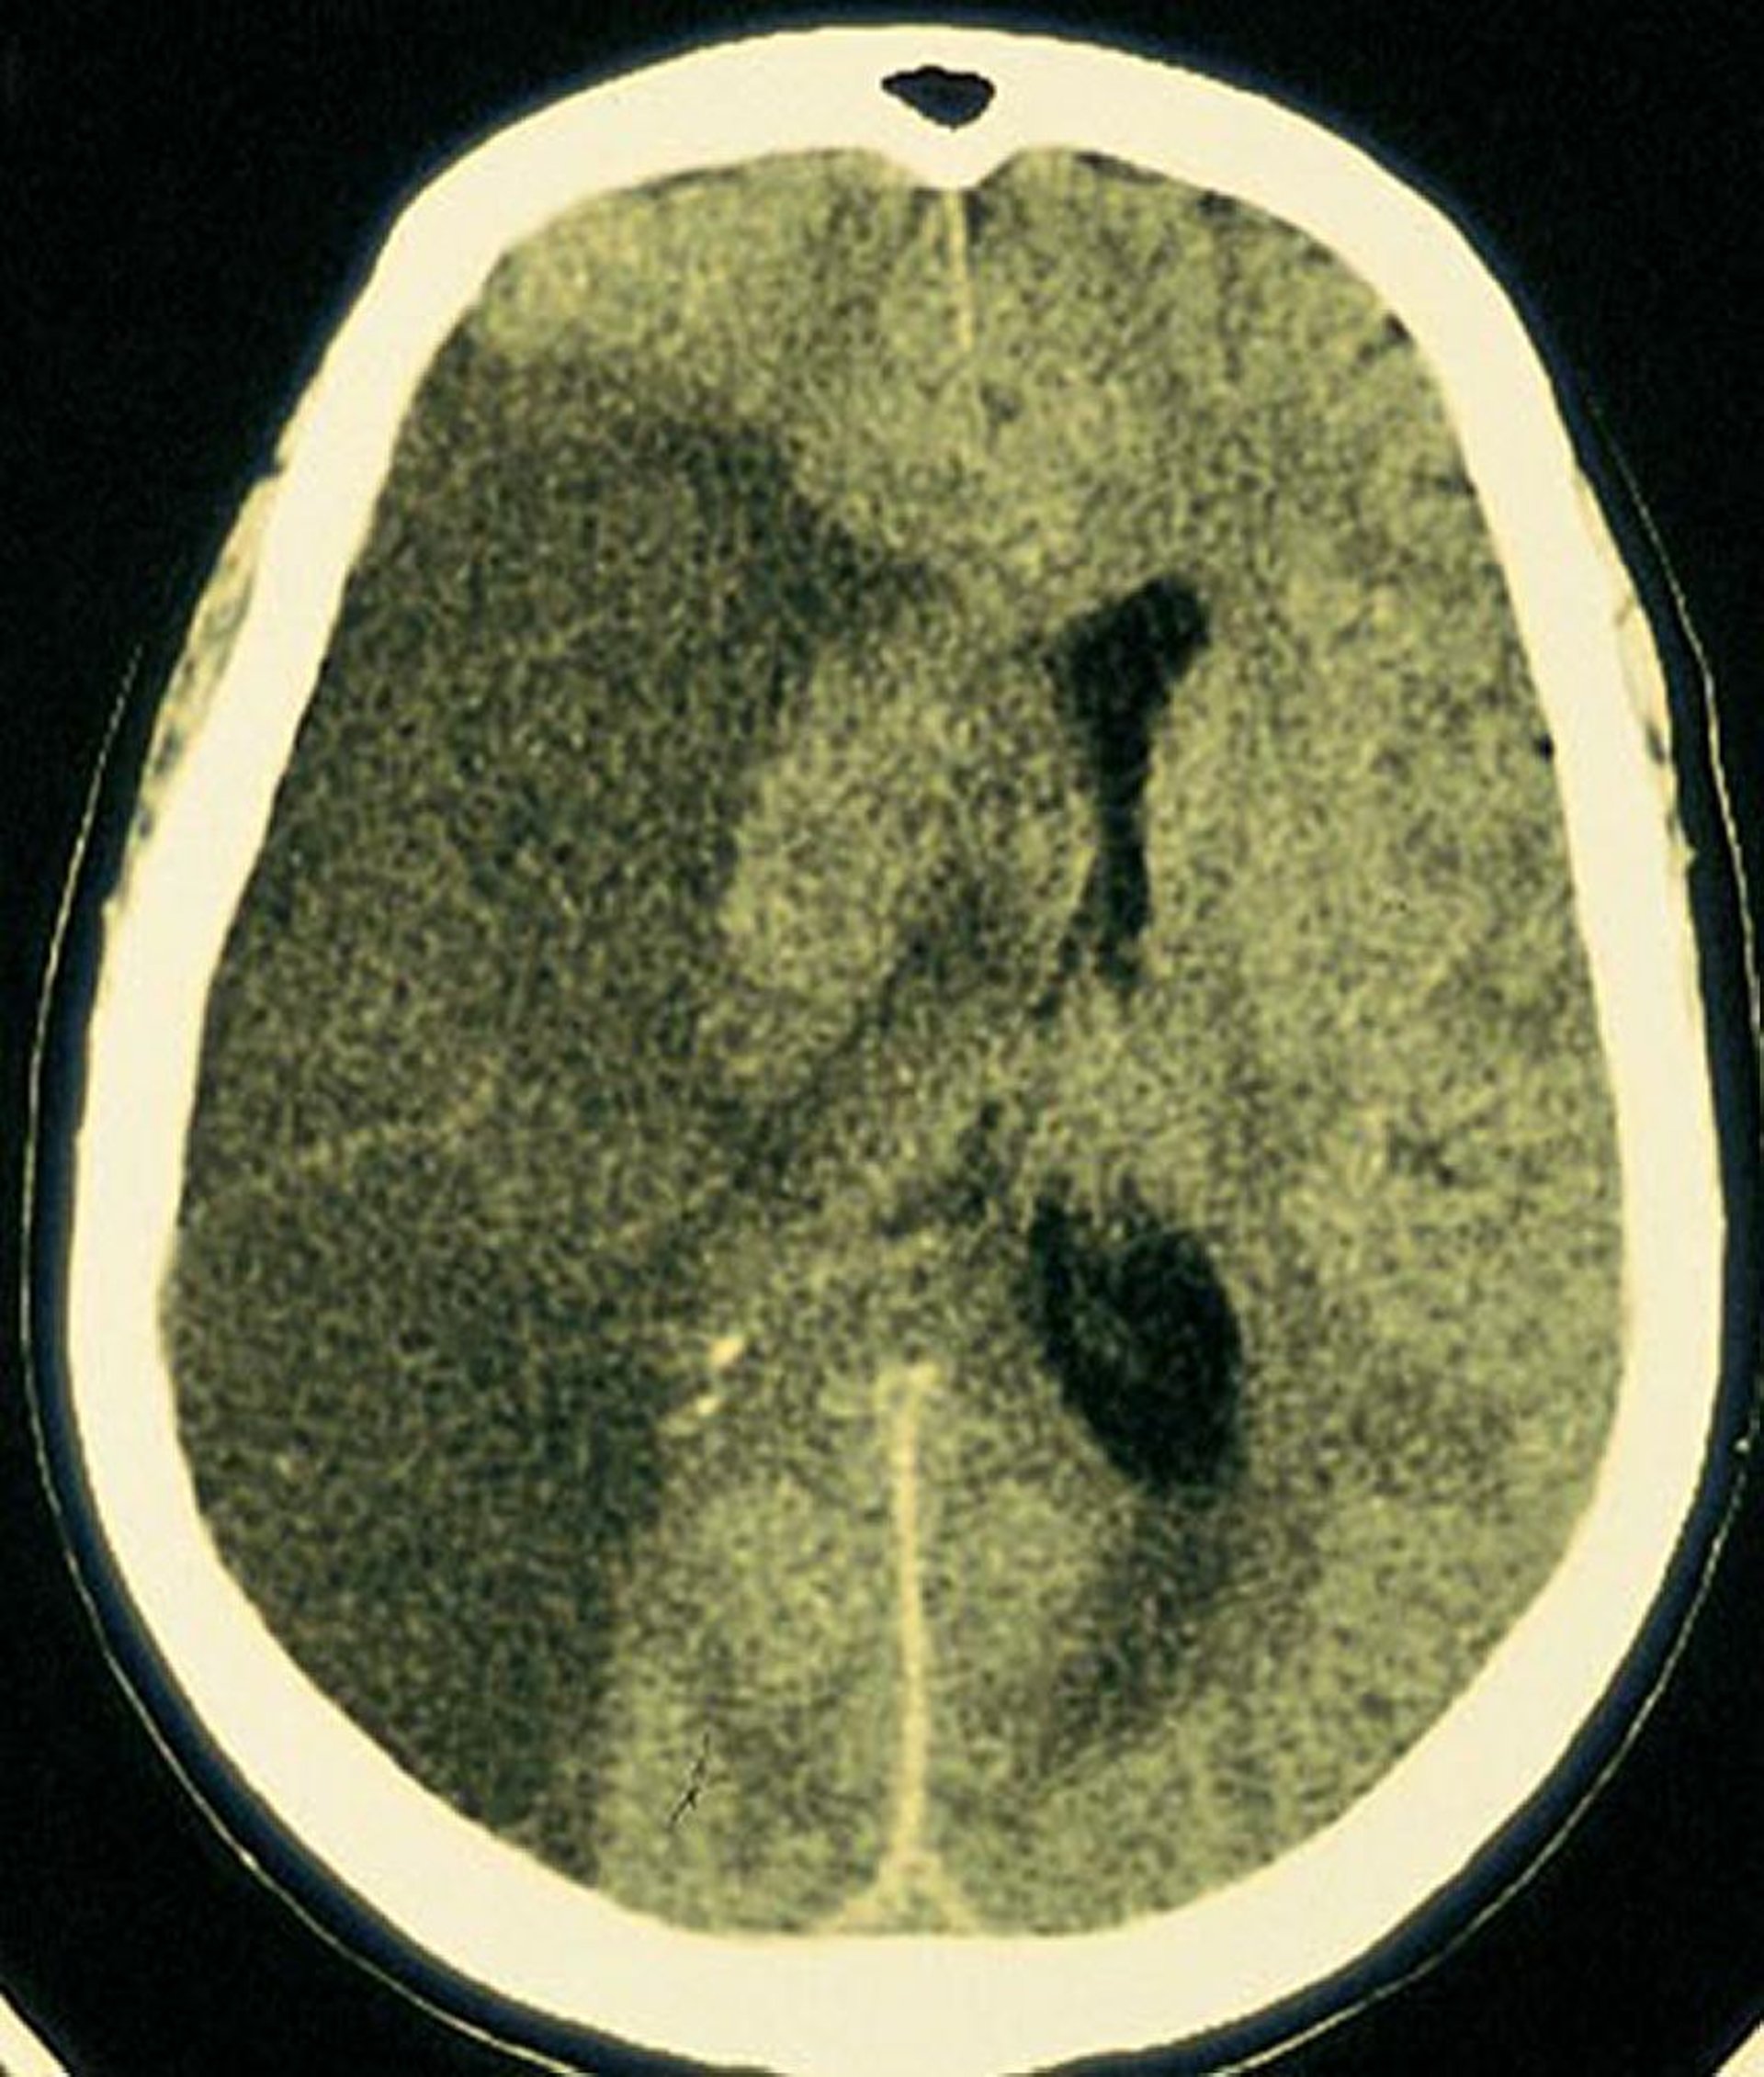

Infarto dell'arteria cerebrale media

Una zona ischemica ampia e lucida si osserva nella zona del cervello perfusa dall'arteria cerebrale media destra.

By permission of the publisher. From Furie K, et al: Cerebrovascular disease. In Atlas of Clinical Neurology. Edited by RN Rosenberg. Philadelphia, Current Medicine, 2002.